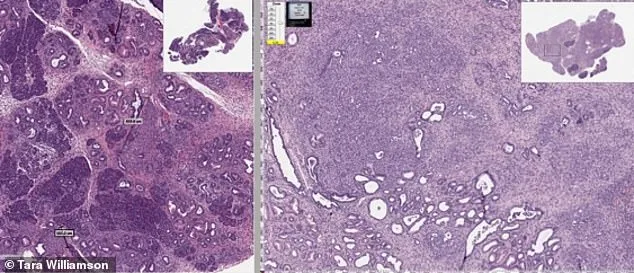

The patent's focus on polymorph C has drawn attention from researchers. Pharmaceutical compounds often exist in multiple solid forms, each with different absorption rates. The patent states formulations with 90% or more polymorph C deliver the drug more effectively, potentially boosting its cancer-fighting power. Scientists believe the drug attacks tumors by disrupting proteins cancer cells rely on for growth, reducing blood vessel formation, and triggering apoptosis—the body's natural cell-destroying process. This multi-pronged approach could make mebendazole a valuable tool in treating aggressive cancers like brain tumors.

Mebendazole has been safely prescribed for decades to treat infections like pinworm and whipworm. Yet recent studies suggest its unique molecular structure may also disrupt cancer growth. The patent highlights polymorph C, a crystalline form that dissolves more efficiently in the body. This improved absorption could allow the drug to reach tumors more effectively, potentially slowing their growth. Early lab trials showed mice with brain tumors lived longer after treatment, raising hopes for human trials. However, the patent's existence has sparked accusations that cancer treatments have been suppressed to protect the multi-billion-dollar pharmaceutical industry.